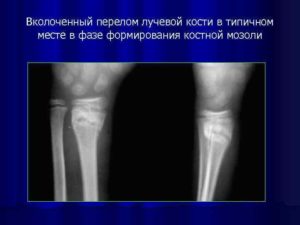

Перелом лучевой кости в типичном месте

У травматологов есть такое понятие, как «перелом луча в типичном месте». Это связано с тем, что подавляющее большинство случаев перелома (почти 75%) приходится на дистальную часть кости (расположенную ближе к кисти руки).

- Консолидирующий перелом является результатом образования на месте линии излома костной мозоли и срастания отломков. При отсутствии своевременной иммобилизации конечности консолидация может быть неправильной: с неполным сопоставлением отломков, нарушением функции конечности, давлением костной мозоли на сосуды и нервы.

В типичном месте

На такую травму приходится более 70% повреждений луча.

Объясняется это тем, что нижняя треть луча представлена губчатой тканью и имеет наименьшую толщину коркового костного слоя, поэтому травмы этой локализации – самые распространенные.

Перелом на дистальном участке (в 2-3 см от лучезапястного сустава) в травматологии именуют переломом лучевой кости в типичном месте.